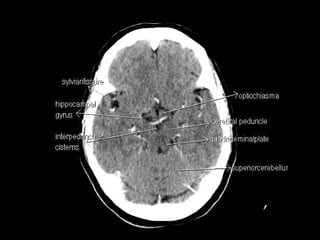

Radiographers use medical imaging equipment like X-rays and MRIs to produce images of patients' internal structures and organs. They are responsible for positioning patients, operating scanning machines, and ensuring quality images. Radiographers must have strong attention to detail, excellent communication skills, and the ability to work well under pressure to accurately capture anatomical features and diagnose any abnormalities.